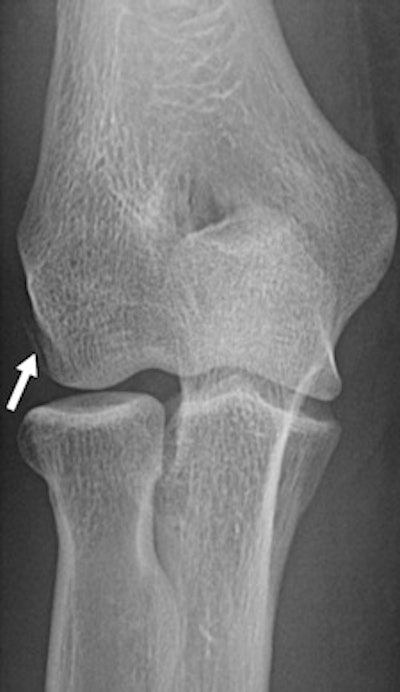

A 22-year-old female boxer who sustained direct blow to elbow during bout. Left: Radiograph of elbow shows avulsion fracture (arrow) of lateral epicondyle. Right: Coronal proton density-weighted fat-saturated MRI shows radial collateral ligament avulsion (short solid arrow). Note edema of lateral epicondyle at site of avulsion (open arrow), complete tear of proximal UCL, and superficial common flexor tendon (long solid arrow).